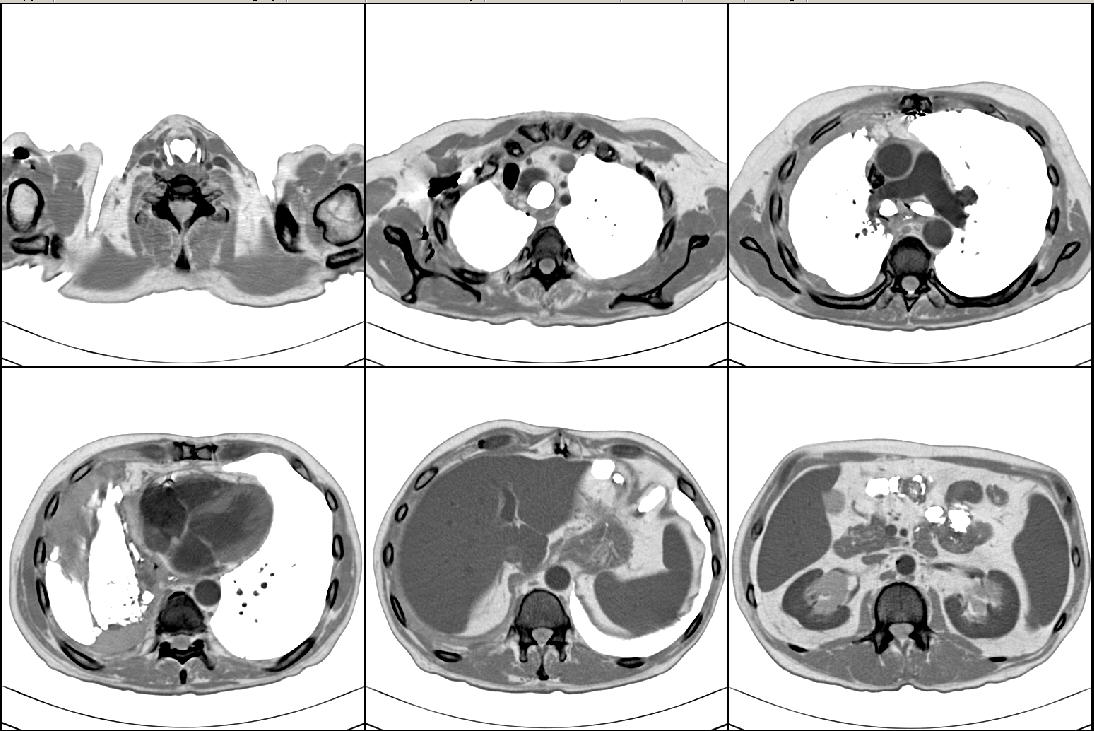

The Cancer Genome Atlas Lung Adenocarcinoma (TCGA-LUAD) 是一个肺癌CT影像数据,源自另一个更大的癌症数据项目 The Cancer Genome Atlas (TCGA),旨在对各种类型的癌症诊治过程进行全程数字化的跟踪,以数字档案的形式记录检查结果、处方和疗效。

| 数据介绍: | The Cancer Genome Atlas Lung Adenocarcinoma (TCGA-LUAD) 是一个肺癌CT影像数据,源自另一个更大的癌症数据项目 The Cancer Genome Atlas (TCGA),旨在对各种类型的癌症诊治过程进行全程数字化的跟踪,以数字档案的形式记录检查结果、处方和疗效。 |